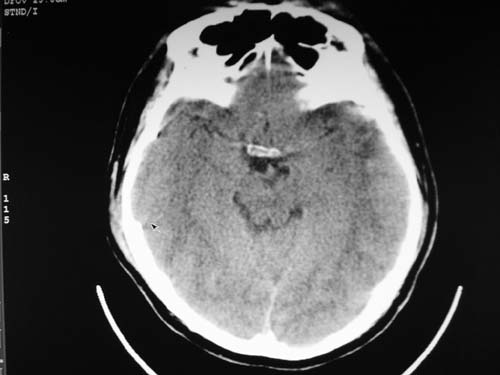

脑中线内血肿,是硬膜下的吗?

脑中线内血肿——硬膜下血肿。

脑中线内血肿——硬膜下血肿。我们一般认为中线即可是硬膜下,也可是蛛网膜下腔的。边缘锐利,张力高的考虑硬膜下的,边缘模糊的,考虑下腔的。如果有老师有肯定的答案,麻烦下给我发个短信

支持镰旁硬膜下血肿,颅骨骨折,头皮损伤.

这个病人年龄不小吧,右侧脑沟不清,中线结构稍有左移,右侧额颞顶及右镰旁硬膜下血肿,另有蛛血,骨折。

外伤后引起的颅骨骨折、硬膜下血肿、皮下血肿,颅骨骨折引起的矢状窦破裂,形成大脑纵裂内血肿。